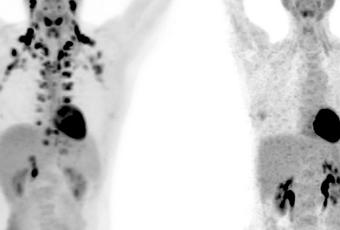

La graisse brune -ou tissu adipeux brun-, contrairement à la graisse blanche, qui stocke des calories, brûle de l'énergie. De nombreuses équipes à la recherche de traitement de l’obésité espèrent parvenir à transformer la mauvaise graisse en tissu adipeux brun. Cependant ce n’est que récemment qu’a été suggérée une association possible entre la graisse brune (à gauche sur visuel) et une meilleure santé. Ensuite, il est difficile d'identifier les personnes qui présentent plus de graisse brune car ce tissu est plutôt situé profondément à l'intérieur du corps.

Il s’agit de la plus large étude menée sur le sujet, soit sur l’association entre la graisse brune et toute une série de résultats de santé. En effet, bien que la graisse brune ait été étudiée pendant des décennies chez les nouveau-nés et les animaux, ce n'est qu'en 2009 que les scientifiques se sont rendu compte qu'elle pouvait être également trouvée en bonne quantité chez certains adultes, généralement autour du cou et des épaules. Depuis, les chercheurs se sont efforcés de comprendre l’action de ces cellules graisseuses particulières, à la capacité de brûler des calories. Avec des limites techniques néanmoins, car la graisse brune n'apparaît que sur les PET scans, un type d'imagerie médicale coûteux qui utilise des radiations. Donc il est difficile de soumettre les participants à ce type d’examen.